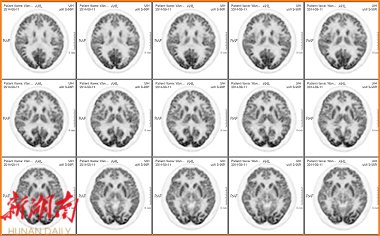

这款PET-CT设备配备了280毫米的超大轴向扫描视野,能够显著缩短扫描时间,提高检查效率。该设备采用的全新数字光导探测器相较于老式PET-CT的普通光导探测器或其他晶体探测器,在分辨率和灵敏度上实现了质的飞跃。凭借1.4毫米的超高清分辨率,该设备能够精准捕捉更微小的病灶,为肿瘤患者的早期发现和治疗提供了强有力的支持。

△超高清分辨率图像,精准显示微小病变

△1.4mm细微结构清晰显像,类MR至真完美图像